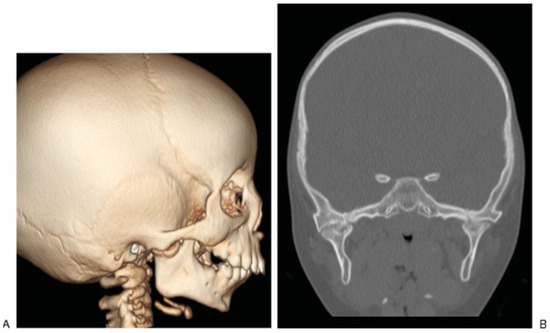

A primary growth center for the mandible is in the condyle, and injury to this area can result in growth disturbance and temporomandibular joint (TMJ) bony ankylosis. Several studies with intermediate-term follow-up have shown good results with conservative treatment of condylar fractures in children [20,42]. Intraarticular condylar head fractures that are displaced laterally are at greater risk of later bony ankylosis to the base of the zygoma [43]. Posttraumatic TMJ ankylosis may present with asymmetry, malocclusion, and limited mouth opening. If the injury occurs as an infant, there may be concomitant retrognathia (Figure 7). TMJ release may be indicated to treat ankylosis, and at the Hospital for Sick Children, this is performed once a patient is old enough to comply with physiotherapy, usually after 6 years of age. The principles of surgical release involve an external approach to the TMJ with excision of the bony block, contralateral bony or soft tissue release as needed, and autogenous reconstruction of the joint. Postoperative physiotherapy is commenced 1 week later and may involve the use of dynamic stretching devices as well as passive bite blocks for nighttime.

Figure 7. (A,B) This patient was injured in a bus crash at age 6 months. Prior to the accident, there was normal mouth opening but over the subsequent 18 months, her mouth opening was reduced to 2 mm. The accident occurred in another country, and her first presentation was at age 2 years with temporomandibular ankylosis.